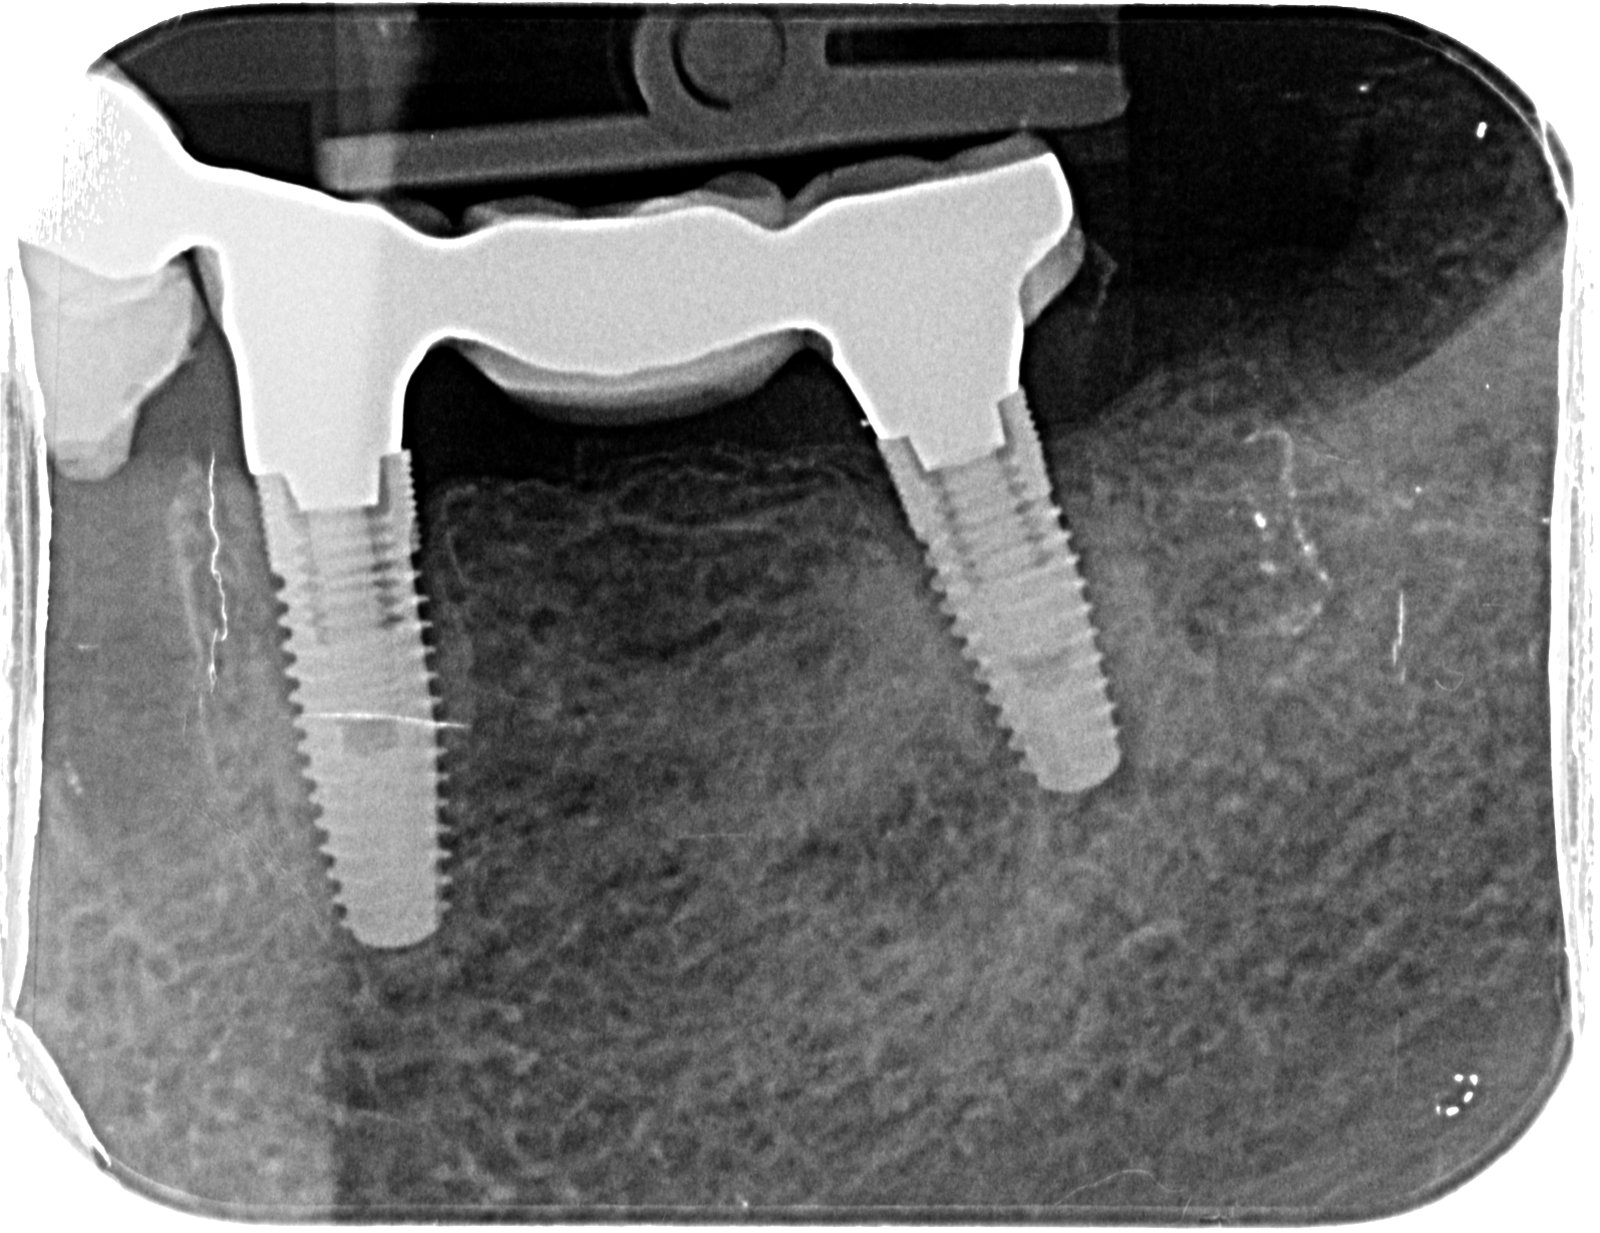

Paciente que acude a mi consulta con la necesidad de cambiar coronas sobre implantes del tercer cuadrante. Implantes conexión interna colocados hace 12 años. He podido soltarlas sin problema con [...]